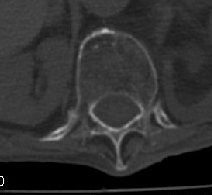

男:89岁因外伤后2天行ct检查。请各位战友讨论图中所指是否是骨折和形成该影像的原因(扫描层面位于椎体中份)。

不象骨折,虽然的双边影,但是椎体前后径没有变化,可能只是骨质增生所致

椎体前缘双边征,其后椎体内密度增高均提示压缩性骨折

压缩性骨折,骨质疏松,前缘密度增高,考虑压缩所致

椎体前缘呈双边征 考虑 压缩性骨折,椎体退行性病变。

虽有双边,单骨皮质完整。